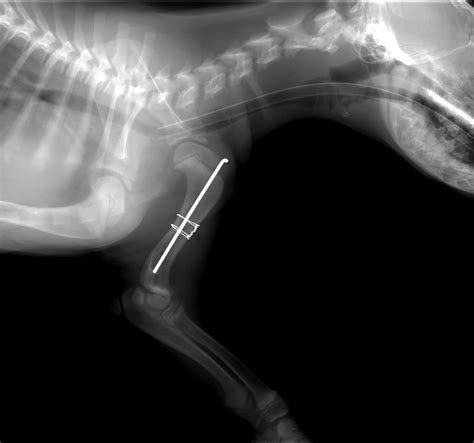

okay, so the vet is hoping the fracture will eventually repair itself without surgery.

Radiographs showed a shepherd's fracture of the talus. What does shepherd fracture mean? okay, so the vet is hoping the fracture will eventually repair itself without surgery. Meaning of shepherd fracture medical term. Eponymous extremity fractures are commonly encountered in the emergency setting. There are many different types of fracture from greenstick, hairline, and compression to oblique, impacted, and longitudinal. Fractures of the entire posterior process of the talus are extremely rare. Looking for online definition of shepherd fracture in the medical dictionary? Dogs · 4 years ago. She responded well to conservative treatment. Well, i went to the doctor/podiatrist for the. Significados de shepherd's fracture en diccionario español inglés : The shepherd fracture is named after the canadian surgeon francis shepherd. They may also be named after an activity with which they are associated. A fracture of the external tubercle (posterior process) of the talus, sometimes mistaken for a displacement of the os trigonum. Radiographs showed a shepherd's fracture of the talus. Hey guys most of you know about my ankle injury about 2 years ago, where i hyper extended my achilles tendon.